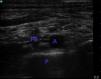

En el postoperatorio presenta dolor severo, sin mejoría a pesar de dosis altas de opiáceos y AINE. Se decide realizar bloqueo supraclavicular bilateral (fig. 2) con levobupivacaína al 0,375% 10cc a cada lado, con lo cual se controla el dolor durante 12h.